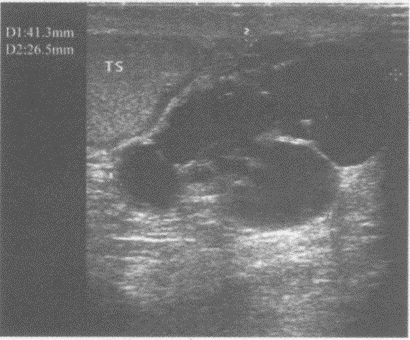

鞘膜积液分四种,如图所示为哪种()。

A:睾丸鞘膜积液

B:精索鞘膜积液

C:睾丸精索鞘膜积液

D:交通性鞘膜积液

E:以上都不是